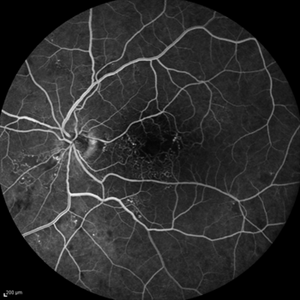

Behcet's Disease Behcet's DiseaseMar 13 2013 by Hamid Ahmadieh, MD Early phase FA of the right eye of a 23-year-old man with retinal vasculitis and branch retinal vein occlusion (BRVO) due to Behcet's disease . Photographer: Solmaz Shahmohammad, Negah Eye Center, Tehran Imaging device: Heidelberg Spectralis Condition/keywords: branch retinal vein occlusion (BRVO), retinal vasculitis